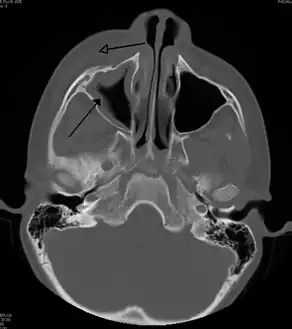

Sinus infection can spread through anastomosing veins or by direct extension to close structures. Orbital complications were categorized by Chandler et al. into five stages according to their severity (see table).[26] Contiguous spread to the orbit may result in periorbital cellulitis, subperiosteal abscess, orbital cellulitis, and abscess. Orbital cellulitis can complicate acute ethmoiditis if anterior and posterior ethmoidal veins thrombophlebitis enables the spread of the infection to the lateral or orbital side of the ethmoid labyrinth. Sinusitis may extend to the central nervous system, where it may cause cavernous sinus thrombosis, retrograde meningitis, and epidural, subdural, and brain abscesses.[27] Orbital symptoms frequently precede intracranial spread of the infection . Other complications include sinobronchitis, maxillary osteomyelitis, and frontal bone osteomyelitis.[28][29][30][31] Osteomyelitis of the frontal bone often originates from a spreading thrombophlebitis. A periostitis of the frontal sinus causes an osteitis and a periostitis of the outer membrane, which produces a tender, puffy swelling of the forehead.

The diagnosis of these complications can be assisted by noting local tenderness and dull pain, and can be confirmed by CT and nuclear isotope scanning. The most common microbial causes are anaerobic bacteria and S. aureus. Treatment includes performing surgical drainage and administration of antimicrobial therapy. Surgical debridement is rarely required after an extended course of parenteral antimicrobial therapy.[32] Chronic sinus infections may lead to mouth breathing, which can result in mouth dryness and an increased risk of gingivitis. Decongestants may also cause mouth dryness.[33]

Infection of the eye socket is a rare complication of ethmoid sinusitis, which may result in the loss of sight and is accompanied by fever and severe illness. Another possible complication is the infection of the bones (osteomyelitis) of the forehead and other facial bones – Pott's puffy tumor.[16]